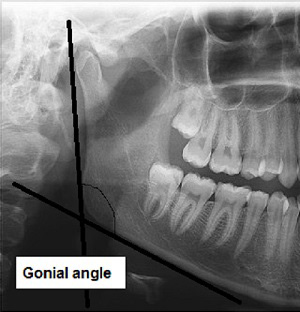

– gonial angle: a line is drawn tangent to the inferior border of the mandibular body, and another line is drawn tangent to the posterior border of the ramus and condyle. The intersection of these 2 lines forms the gonial angle (Figure 1)18;